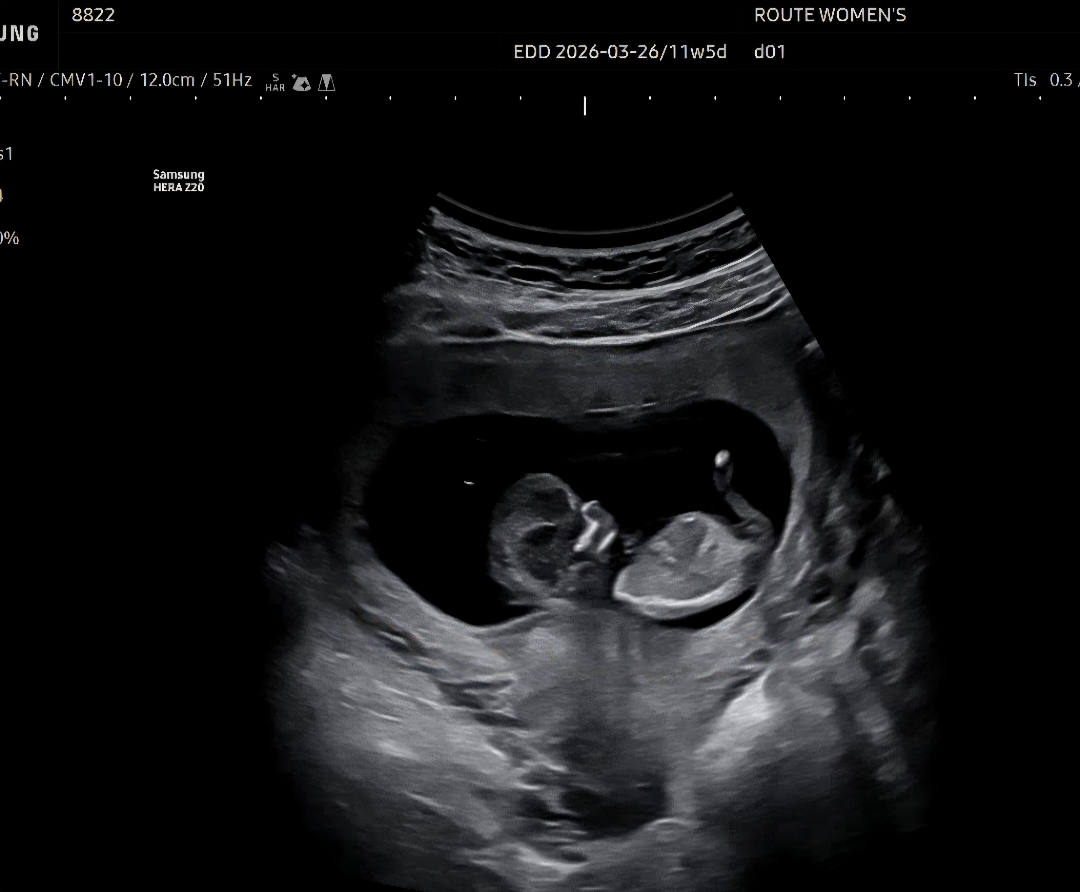

11주5일차 초음파 성별 혹시 보이실까요?

각도법으로 혹시 이 사진으로 성별 확인되나요?